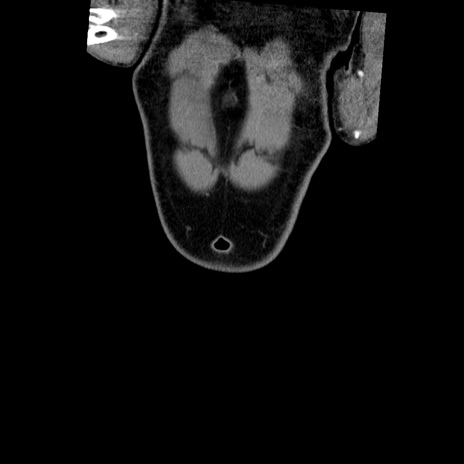

横断像

【症例】50歳代男性

【主訴】腹痛

【現病歴】AVMからの被殻出血のため回復期リハ病棟入院中。 本日午後3時頃急に下腹部痛が出現した。

【既往歴】AVM、被殻出血、虫垂炎、高血圧

【身体所見】意識晴明、左半身不全麻痺、会話の理解は良好、36.5°C、腹部:膨隆、全体に板状硬、下腹部正中に圧痛点あり、反跳痛-、筋性防御不明、右下腹部にope scar

【データ】WBC 9400、CRP 0.06